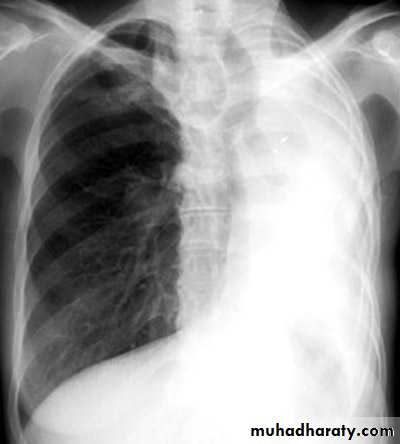

Massive pleural effusion